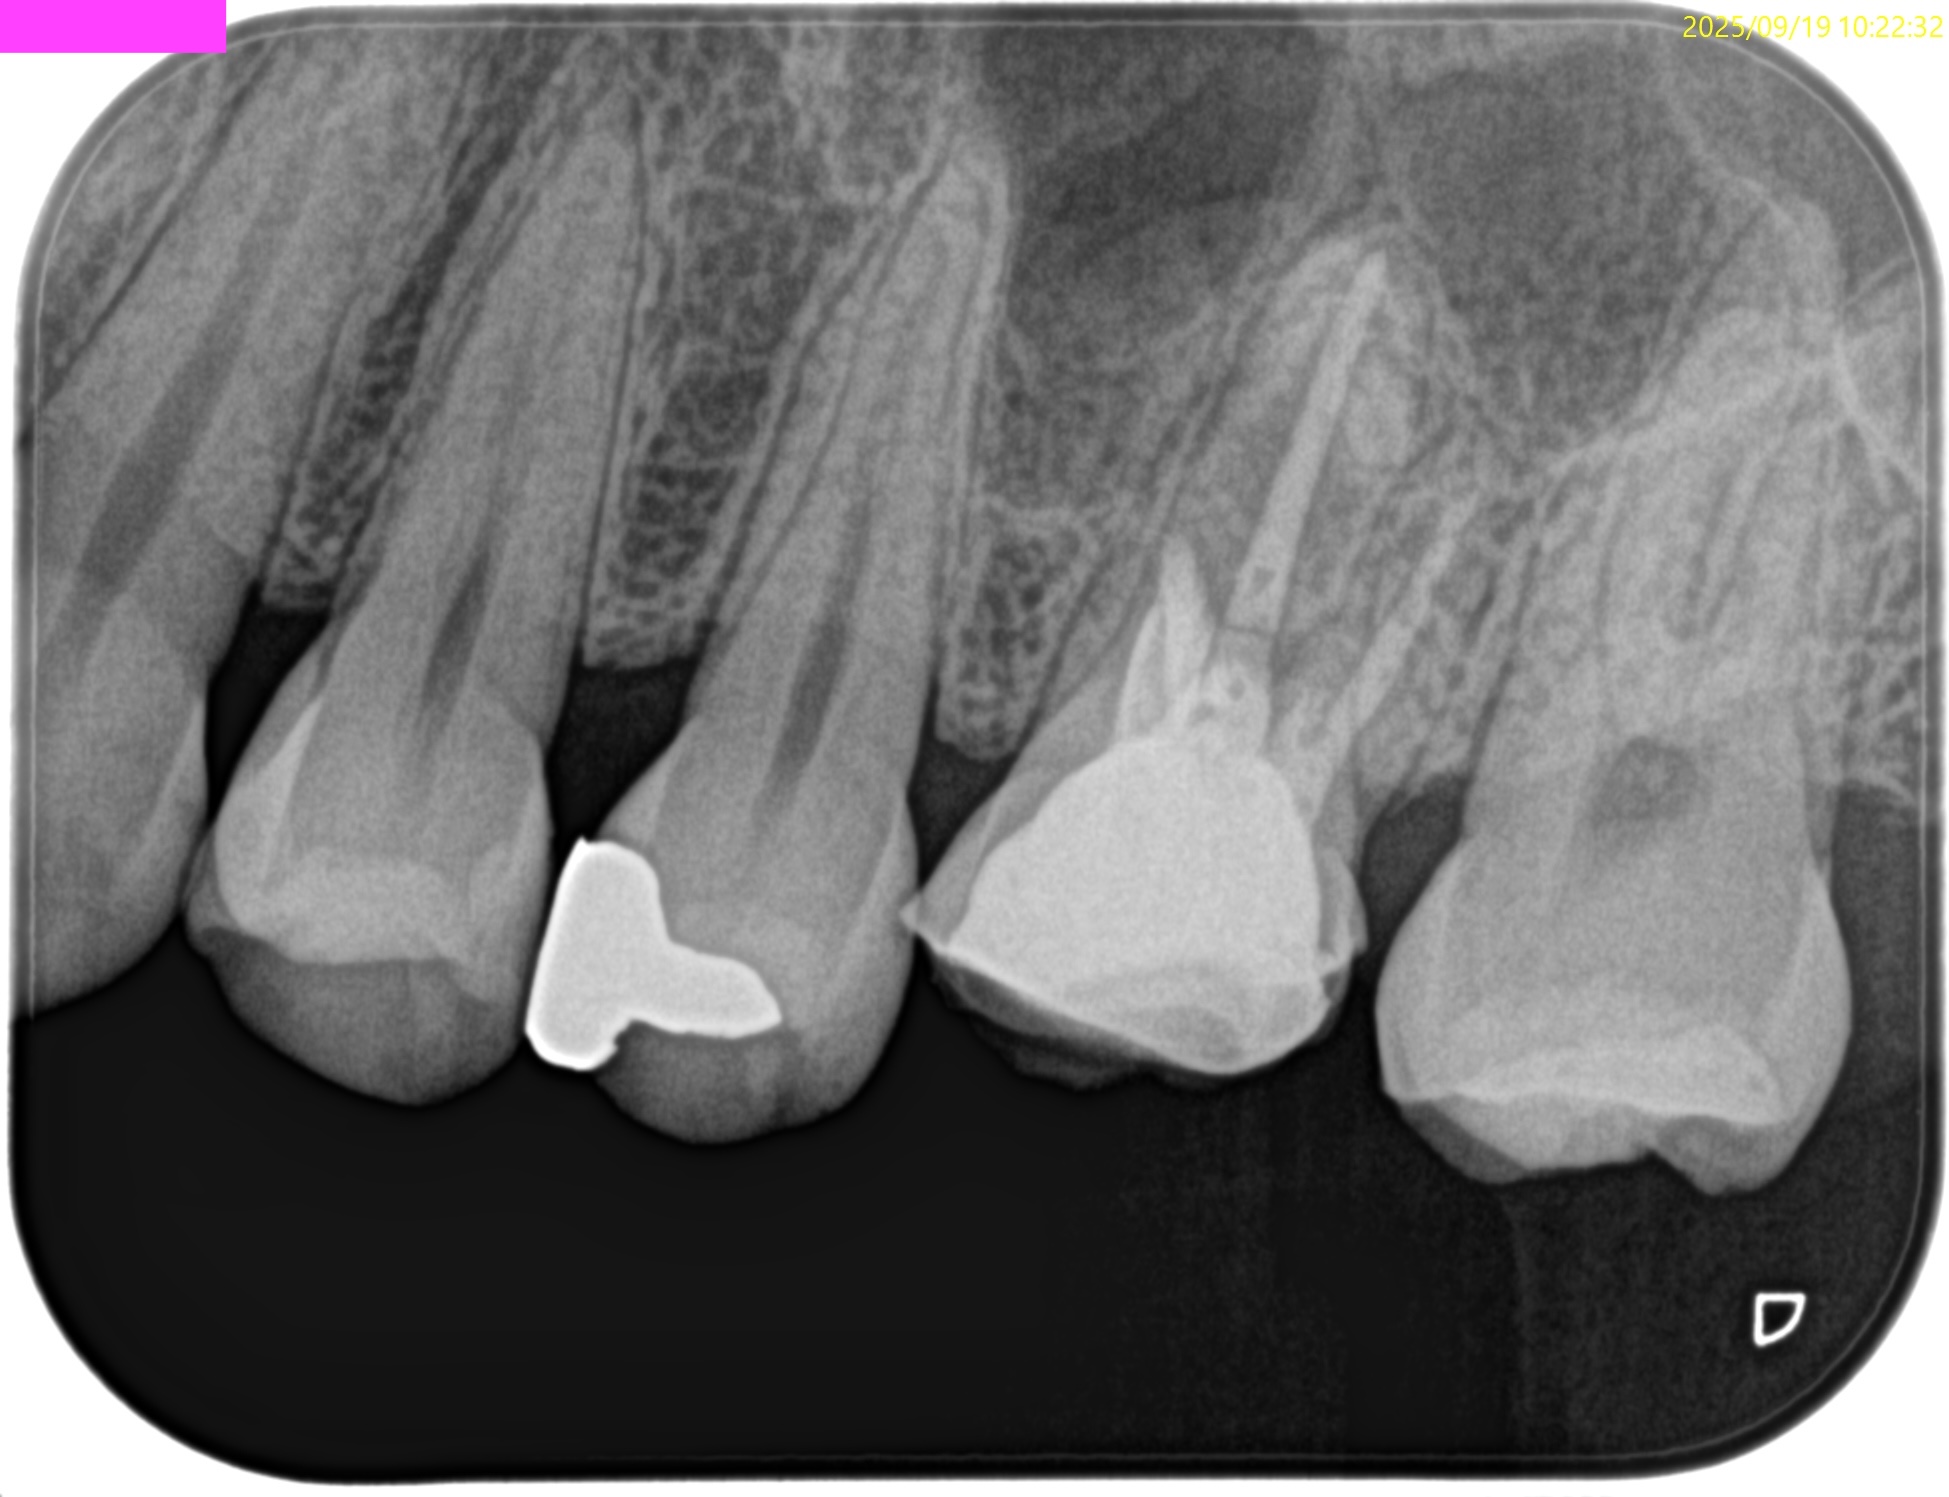

#14 Apicoectomy 4M recall(2025.9.19)

痛みは再現できなかった。

というよりなかった。

術直後と比較した。

大幅に状況が改善している。

治癒が早い人なのだろう。

次回は1年後である。